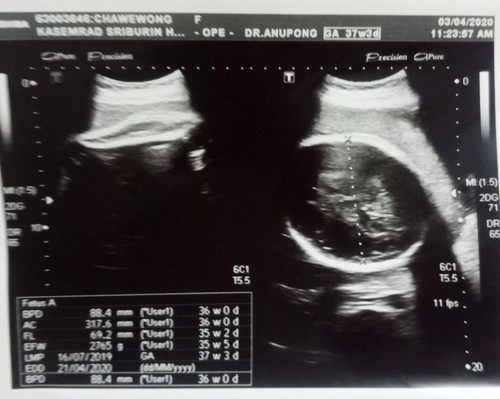

เด็กตัวใหญ่เกินเครียด

วันนี้33weekแต่ขนาดและน้ำหนักลูกเท่ากับเด็ก 37weekหมอสั่งงดข้าว ให้กินแต่ผักผลไม้ น้ำเปล่า กินได้ตั้งแต่8:00-18:00น. เครียดด้วยหิวด้วย ใครเคยมีปัญหาแบบนี้บ้าง